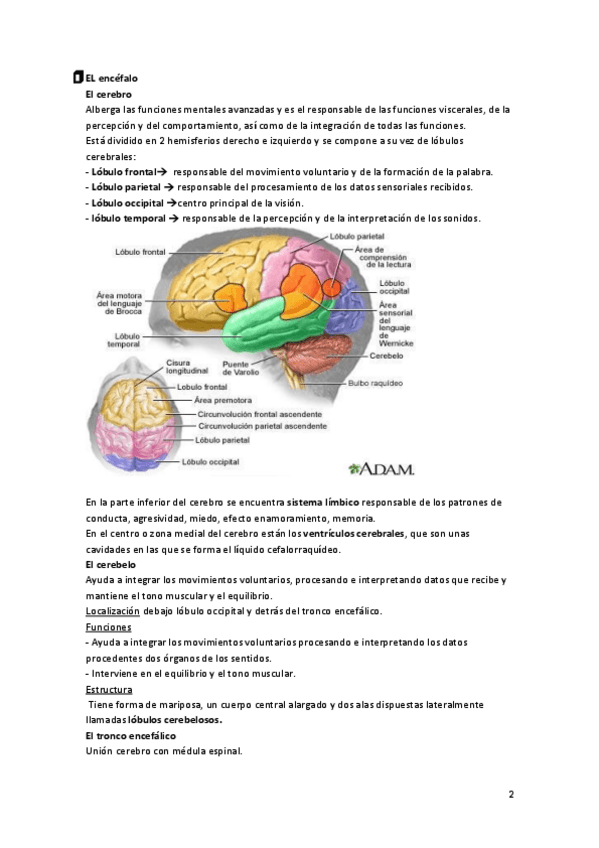

He publicado nuevos apuntes de Fisiopatología general: Tema-7-Fsiopatologia-neurologica.pdf